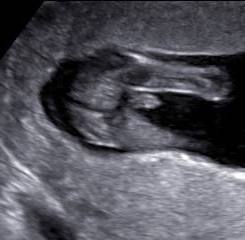

Een pretecho kan vanaf 6 weken zwangerschap gemaakt worden.